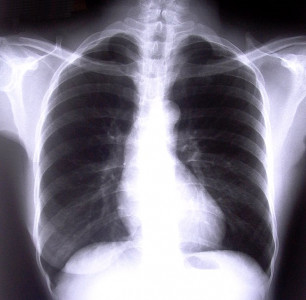

A TB centre in Ojha that doesn’t believe in just treating the illness

Doctors at the Ojha Institute of Chest Diseases have learnt that skills training goes a long way.

World No Tobacco Day: In Pakistan, the cancer continues to spread

Smoking in restaurants pollutes the air four times over the WHO limit.